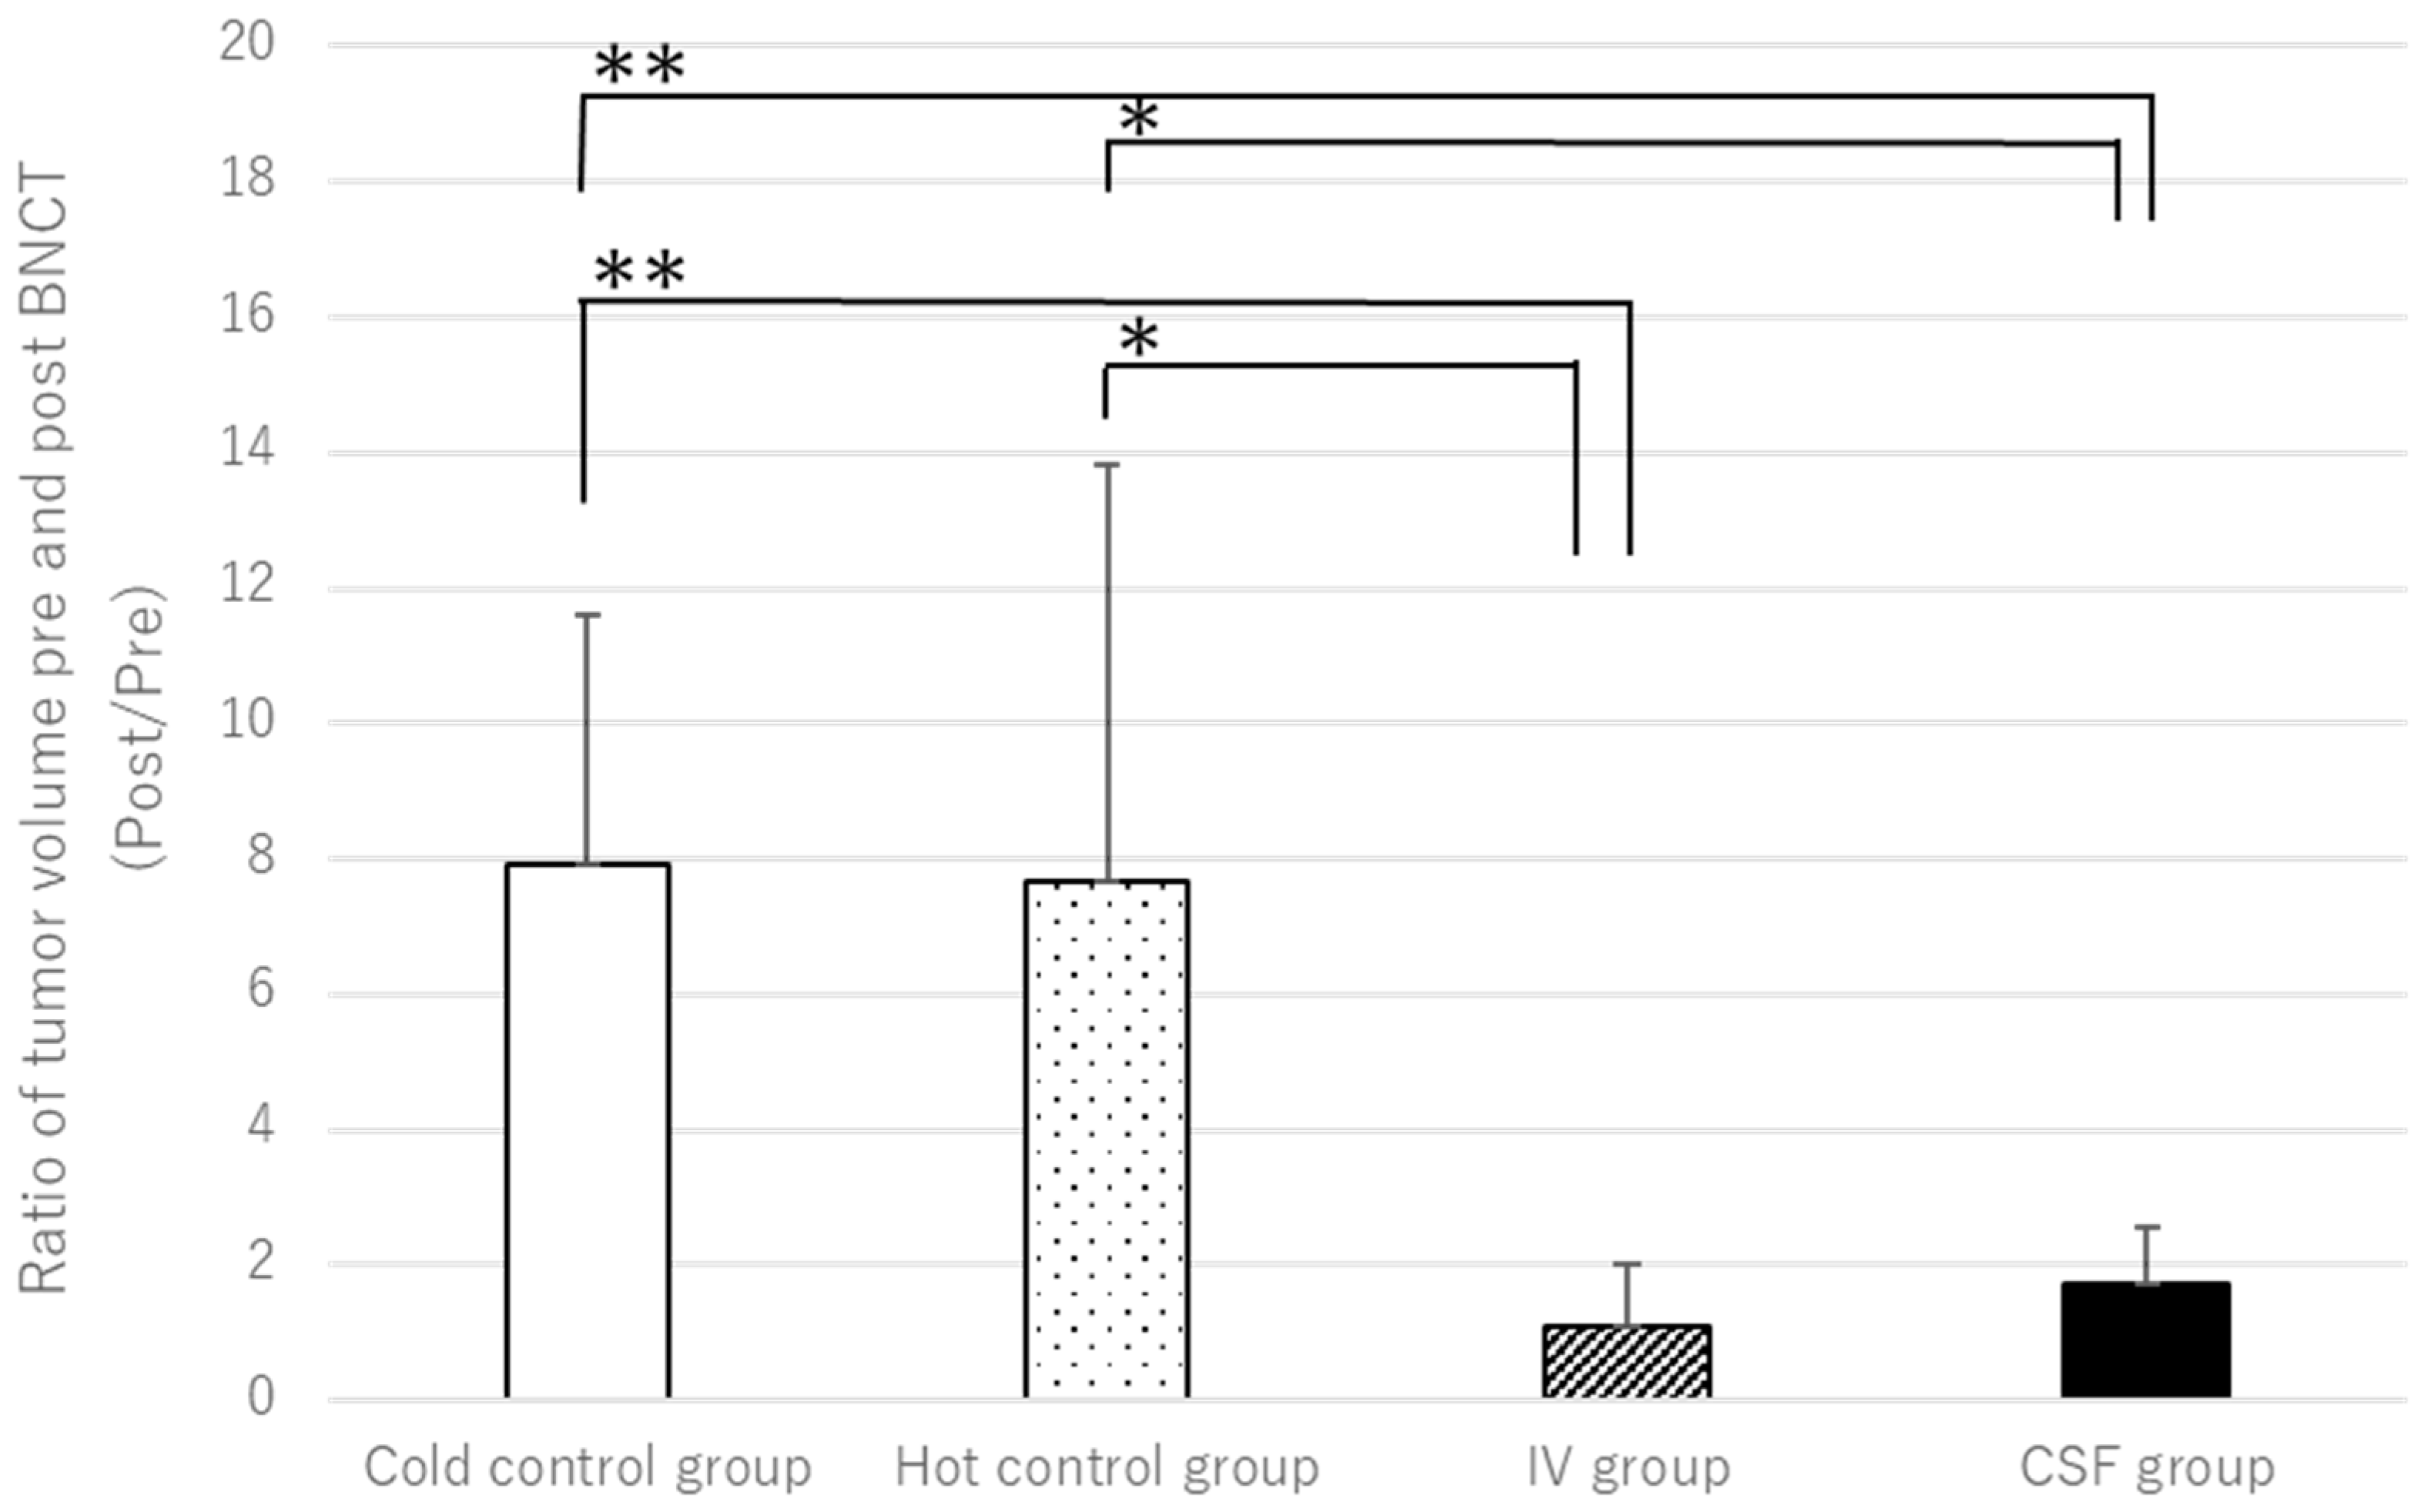

2.2. BNCT Effect on the CSF Administration Method of 10BPA

2.3. Pre- and Post-Treatment MRI Assessment

2.4. Hematoxylin and Eosin Staining of C6 Rat Glioma Brain Sections

3. Results

| Day 0 * | Day 7 | Day 10 | Day 17 | |||

|---|---|---|---|---|---|---|

| C6 Cell Transplantation | MRI (Pre-BNCT) | BNCT | MRI (Post-BNCT) | HE Staining | ||

| BPA | Irradiation | |||||

| Cold control group ** | ◯ | A | - | - | A′ | A″ |

| Hot control group *** | 〇 | B | - | 20 min | B′ | B″ |

| IV group | 〇 | C | 350 mg/kg | 20 min | C′ | C″ |

| CSF group | 〇 | D | 16 mg/kg | 20 min | D′ | D″ |